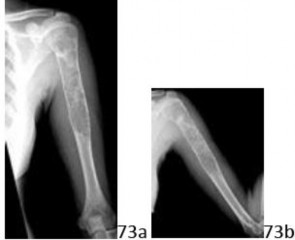

19a 19b A 15-year-old girl injured her shoulder in a fall while riding her bicycle. She reports a mild ache over the latter aspect of the shoulder, present since the accident, but denies any prior shoulder symptoms of any kind. AP and lateral radiographs shown in Figures 19a and 19b reveal a lesion in the proximal humerus. What is the most likely diagnosis?

DISCUSSION: This scenario represents the common "serendipitous" finding of benign chondroid lesions. The radiographs demonstrate the classic "rings and arcs" calcification of an enchondroma, in a commonly

presenting location (proximal humerus). The lesion is generally centrally located, and may have a well-defined lucent appearance, typically in the metaphysis of the bones. The other lesions listed do not have the typical calcification seen in these chondroid lesions. The mineral density in an osteoblastoma is more sclerotic and the lesion is often destructive. An aneurysmal bone cyst is purely lytic and generally expansile. Osteochondroma is an exophytic lesion, protruding outside the bone. Nonossifying fibroma is an eccentric, well-demarcated lesion with no mineral density. The Preferred Response to Question # 19 is 3.